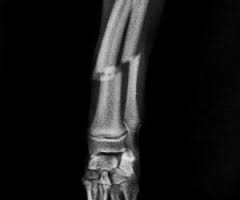

Cuando se habla de fractura se hace referencia a un daño al hueso, es decir, cuando se rompe el cartílago o hueso. Son múltiples los factores que pueden generar fracturas en gatos pero los más comunes en este animal son los golpes y traumatismos.

Cualquier hueso puede sufrir una fractura, sin embargo hay unos que pueden ser más sensibles que otros como lo son tibias, fémur, entre otros.

Son múltiples las fracturas en gatos que pueden existir, sin embargo estas se pueden clasificar en cuatro tipos de fracturas, según la intensidad de cada una.

Fractura de tallo verde

En primer lugar vamos a mencionar a la fractura de tallo verde, está básicamente consiste en una grieta en el hueso, pero este no se encuentra roto.

Fractura abierta

En segundo lugar tenemos a la fractura abierta, esta consiste en la ruptura del hueso y adicional a esto se puede ver a simple vista. Es considera una de las más complicadas, ya que si no tiene los cuidados necesarios se puede infectar.

Fractura cerrada

Otra de las fracturas que se encuentra en la lista es la fractura cerrada, en este caso el hueso se encuentra roto, pero no existe ningún tipo de daño a la piel.

Fractura epifisiaria

La cuarta es la fractura epifisiaria, es una de las más comunes en los gatos. Esta tiene lugar cuando el cartílago de crecimiento sufre algún daño, es decir, se rompe.